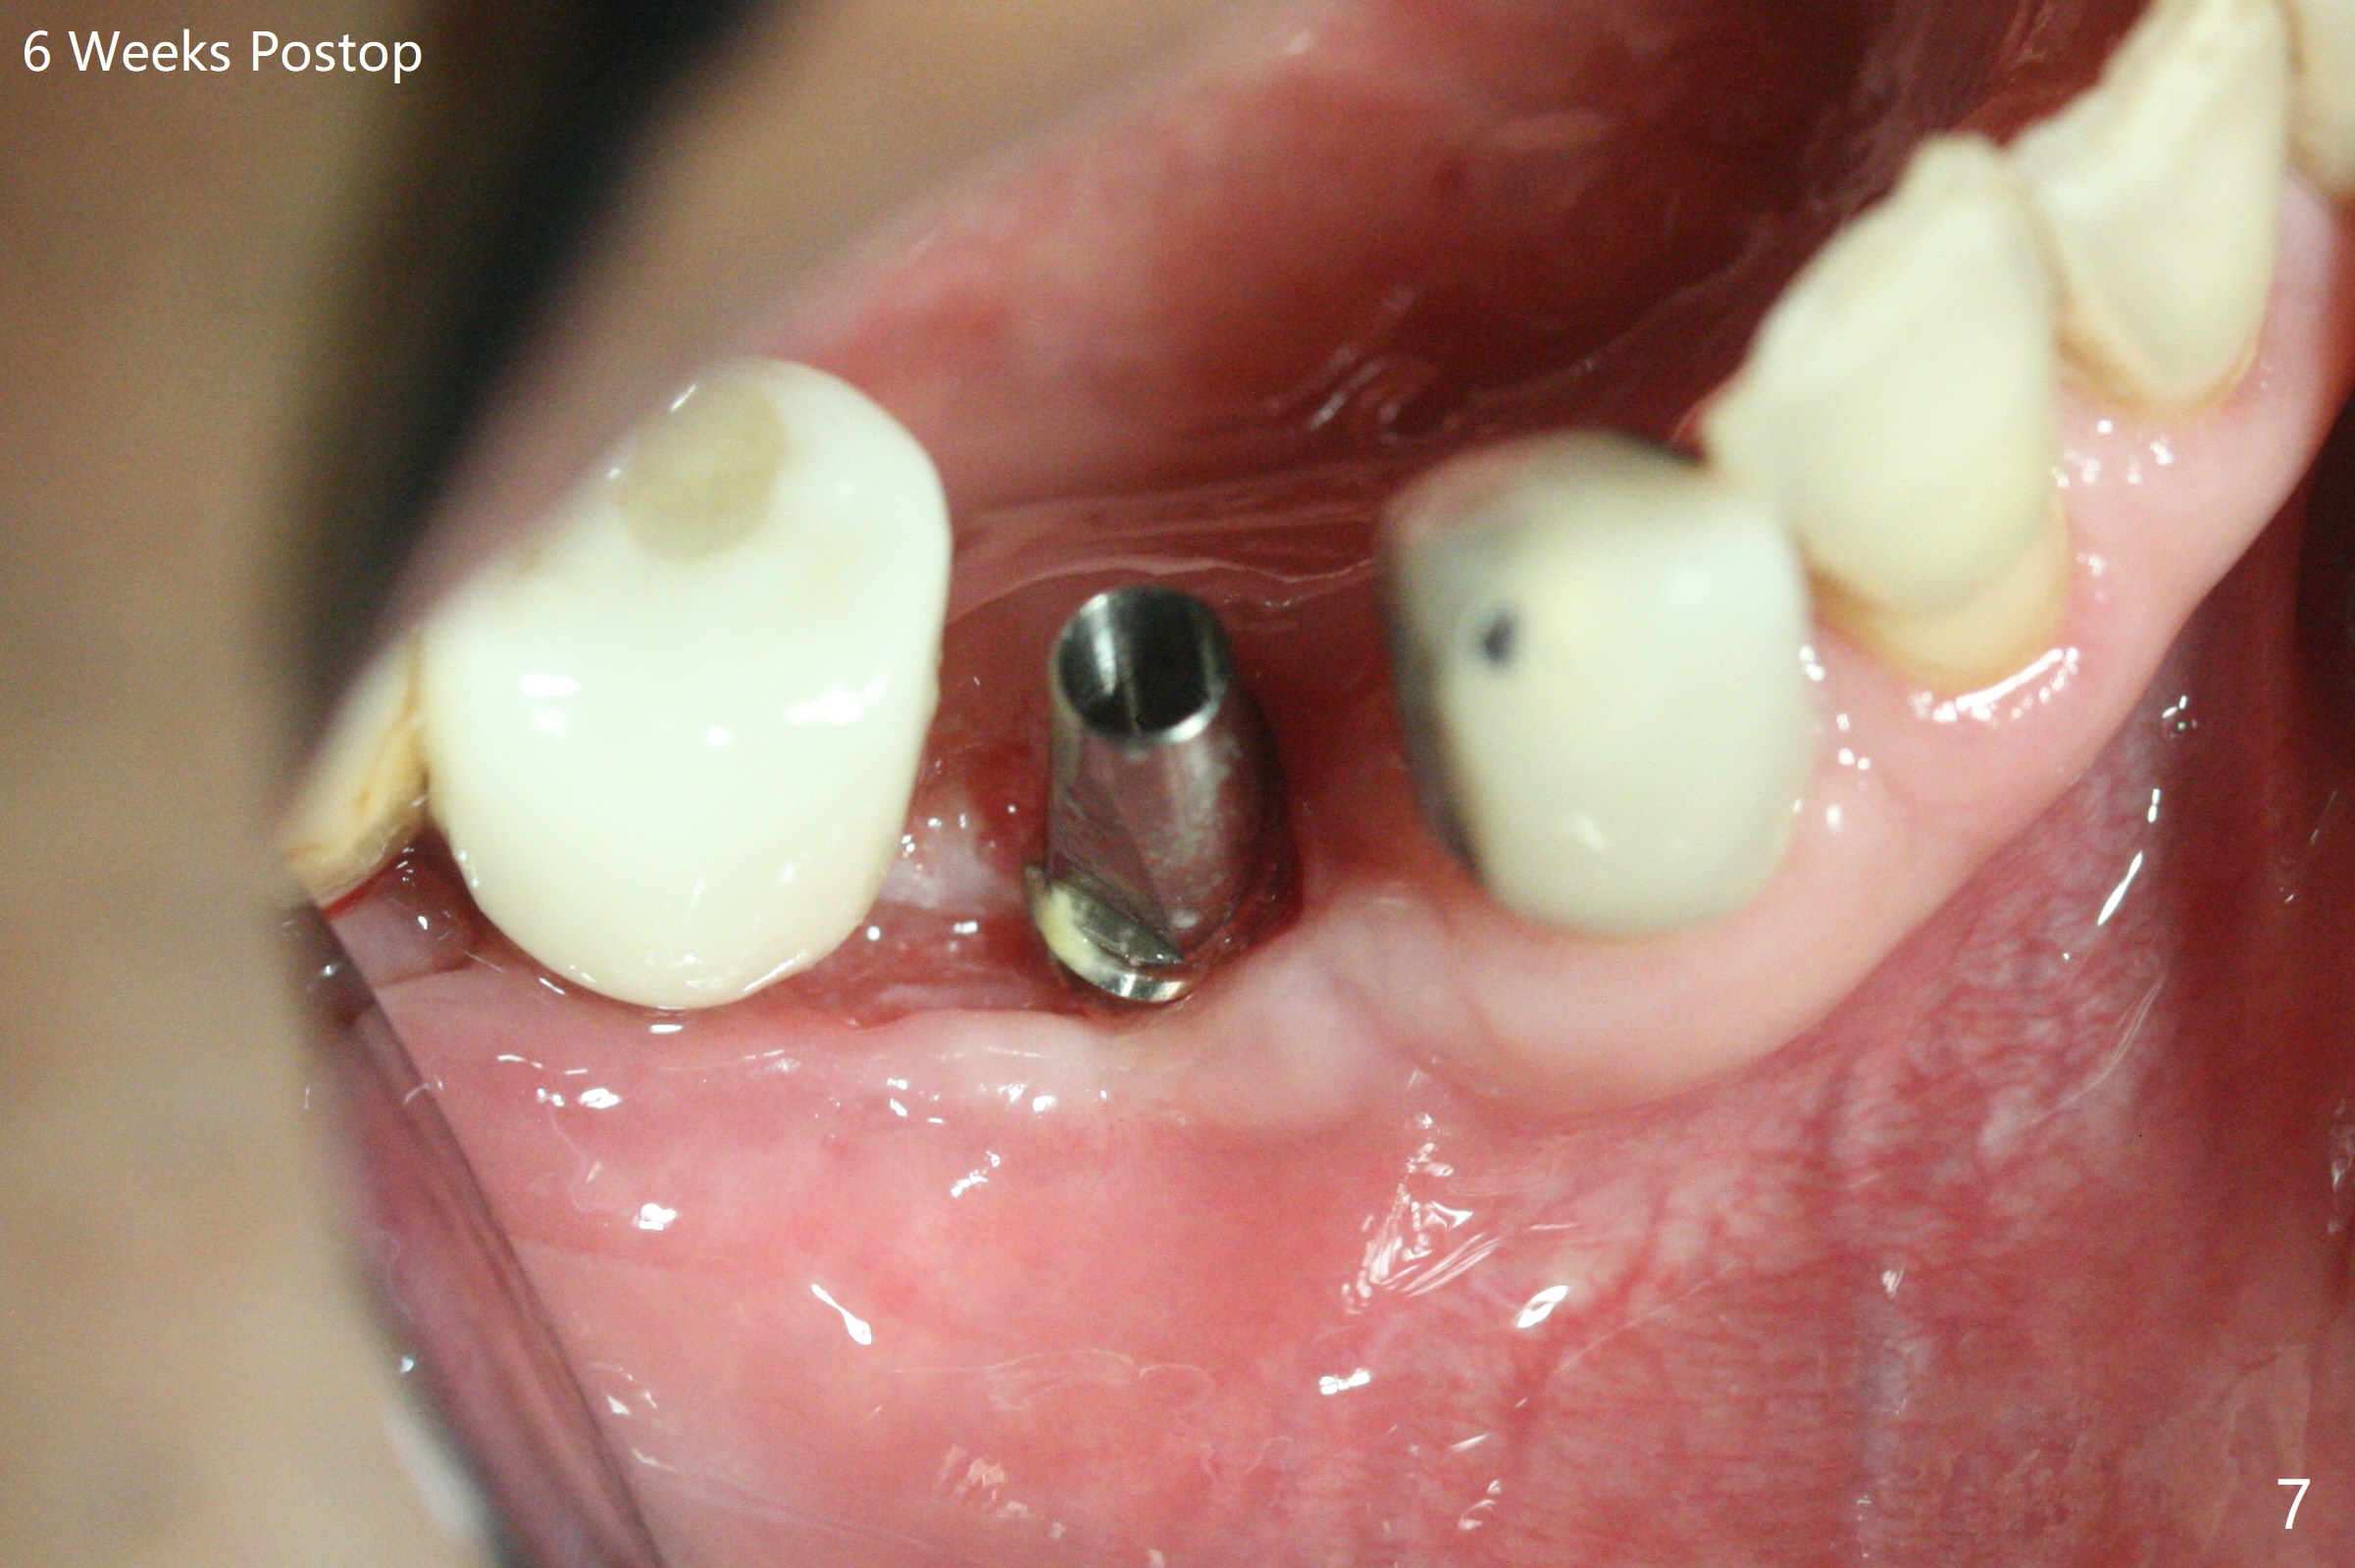

28牙位3.5x8.5毫米植体导板植入后,颊侧远中螺纹暴露,为了植骨,附近骨壁钻洞创造出血点以及放置基台(图一:5x7.5(3)毫米)。放置粘性骨粉后(图二:*),覆盖薄层PRF,后者可能很快吸收,为了防止骨粉暴露,放置不可吸收膜(图三:*),当中打洞,穿过基台固定,表面缝合。术后六周不可吸收膜部分暴露(图四)。图五,六显示在取出时膜当中固定用的洞,下面伤口愈合正常(图七)。